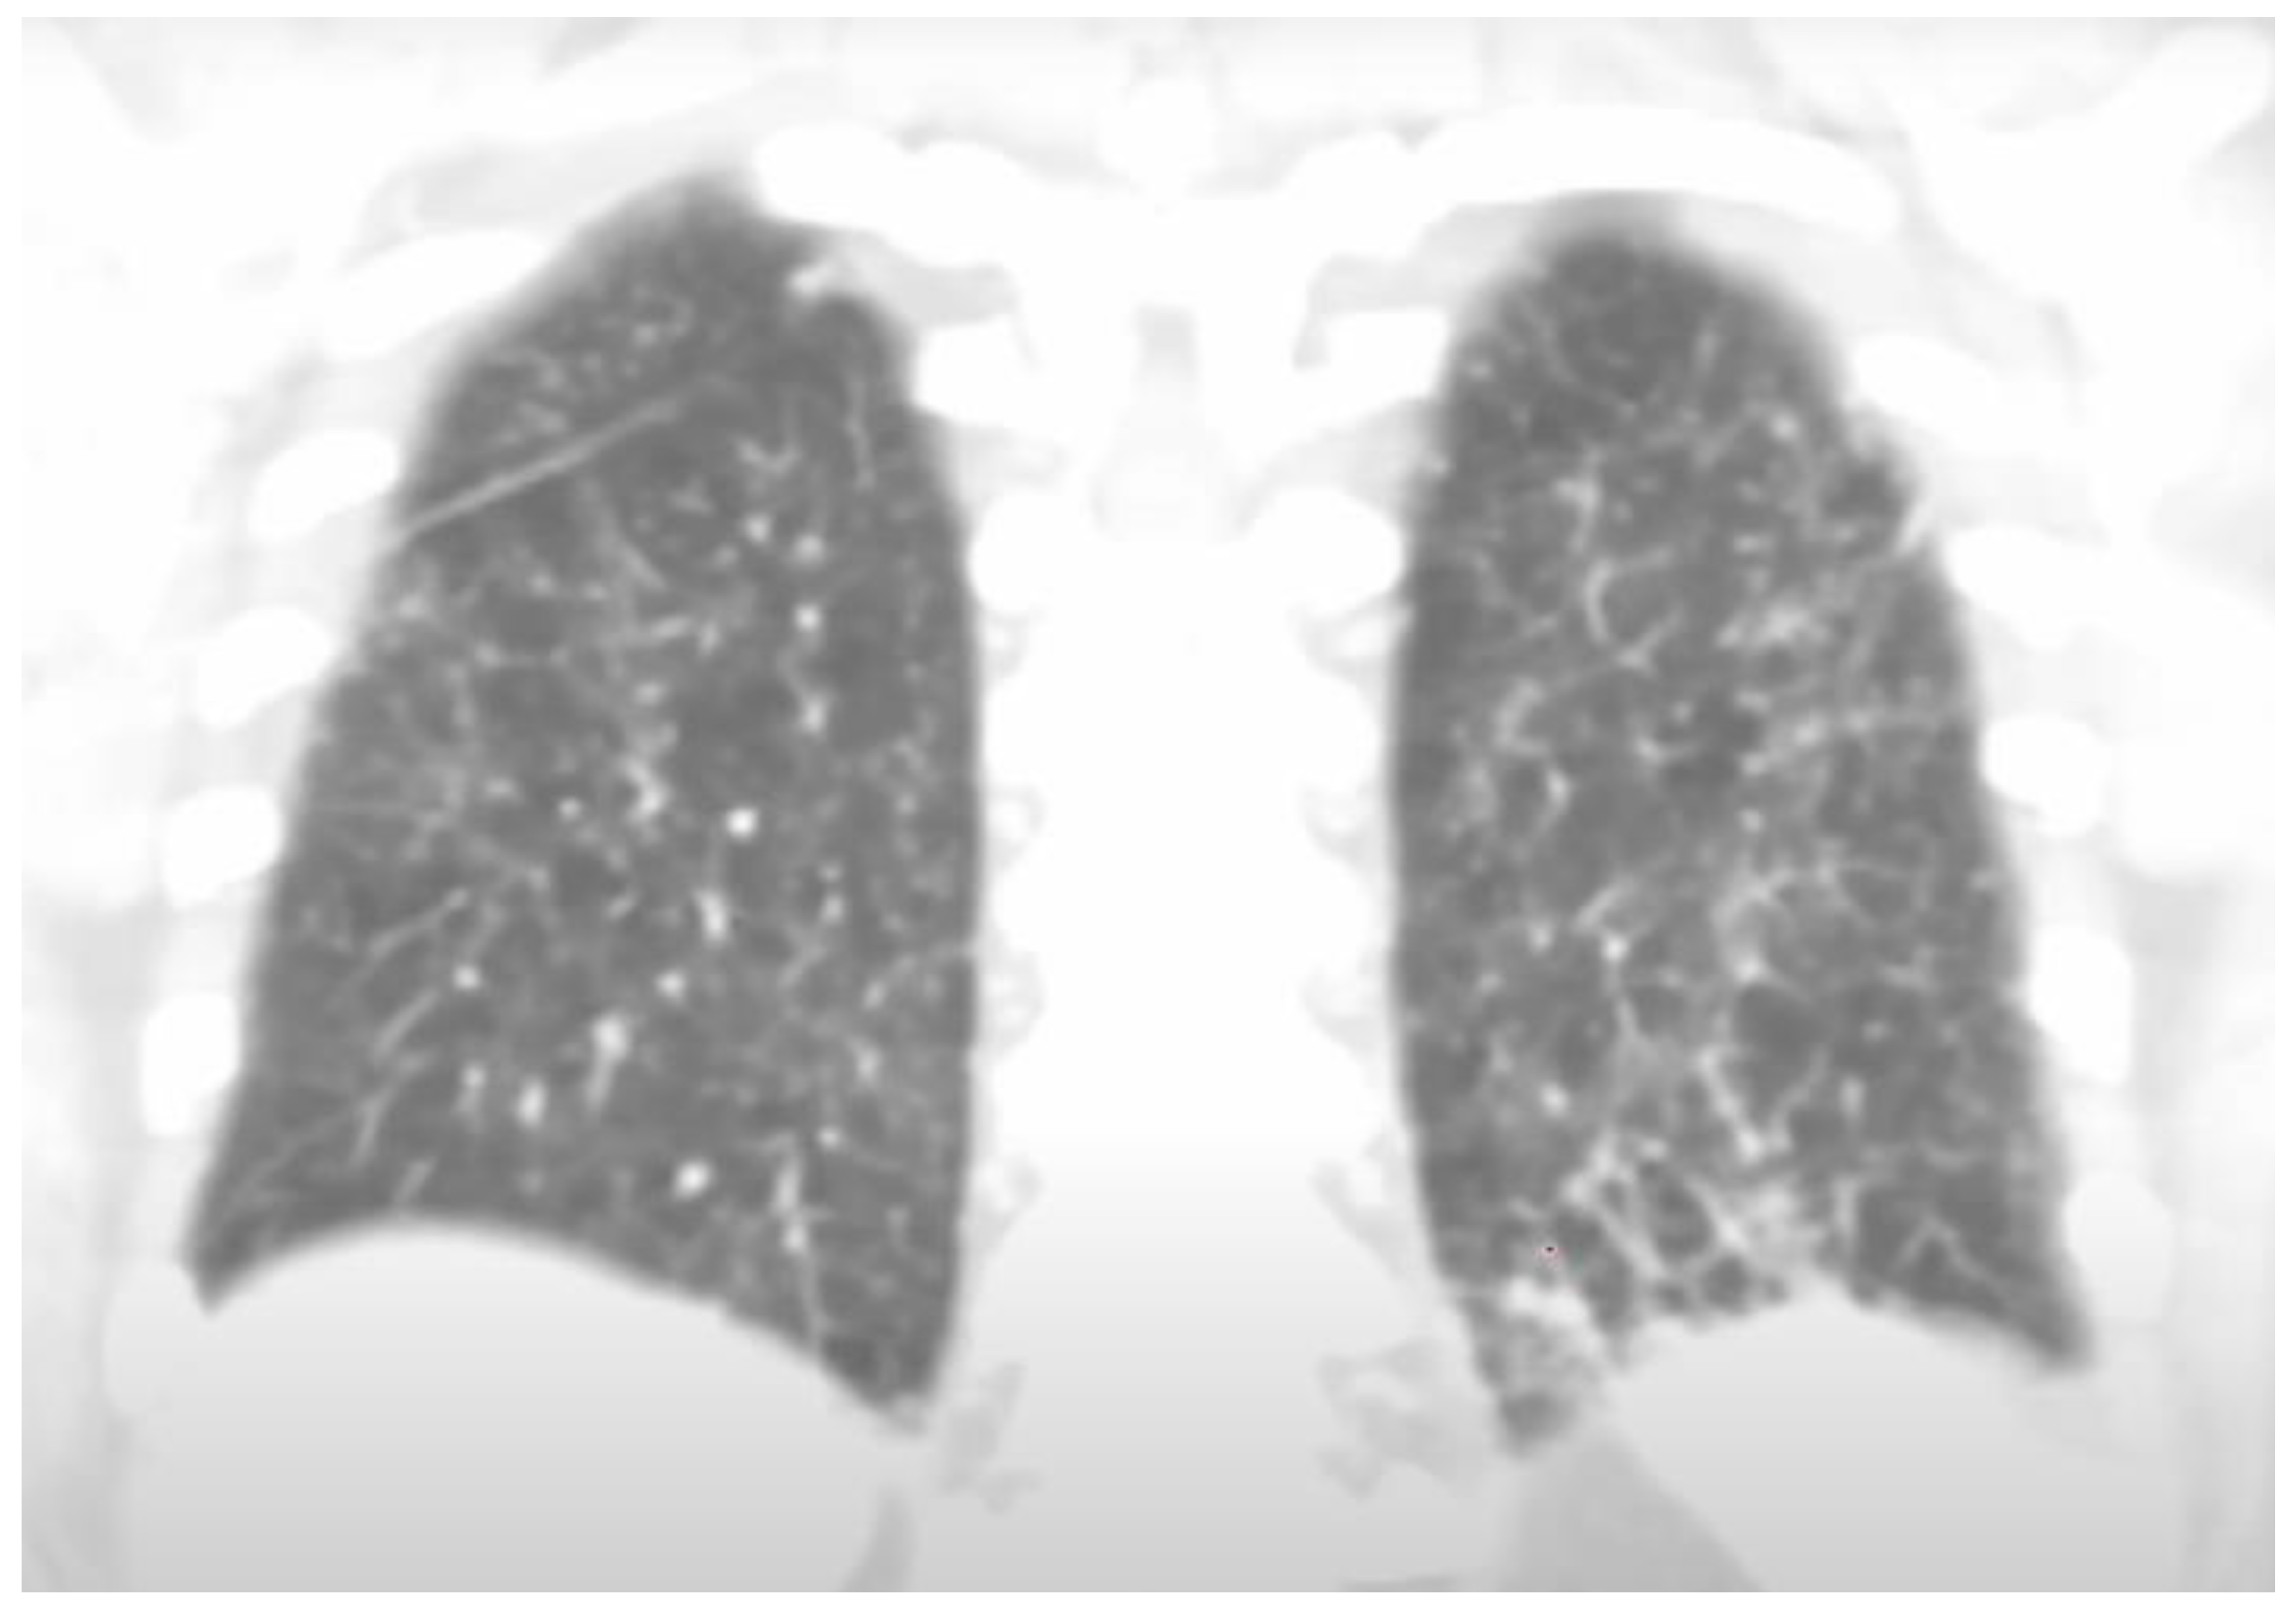

Background: Overlapping endemic infections often present with non-specific systemic features, which could initially lead to delayed recognition and inappropriate treatment. Strongyloides stercoralis and Coccidioides spp. are rarely encountered together, yet both may cause pulmonary disease, constitutional symptoms, and eosinophilia, complicating diagnosis. Corticosteroid exposure in particular can unmask severe strongyloidiasis, highlighting the importance of early detection. Case Presentation: We present the case of a 30-year-old man from the Dominican Republic with recent travel to Brazil and Mexico, who presented with a 3-week history of fever, cough, myalgias, rash, and 13-pound weight loss. Initial treatment for presumed asthma exacerbation and bacterial pneumonia with corticosteroids and multiple antibiotics failed to relieve symptoms. Laboratory evaluation revealed marked eosinophilia (absolute eosinophil count 3,400/µL) and elevated inflammatory markers. Chest CT demonstrated diffuse bilateral tree-in-bud and micronodular opacities. Bronchoalveolar lavage contained 44% eosinophils. Serologic testing was positive for Strongyloides IgG, Coccidioides IgM/IgG, and β-D-glucan. The patient improved with ivermectin and fluconazole but experienced a relapse of coccidioidomycosis after antifungal discontinuation, requiring reinitiation of long-term azole therapy. Discussion: Coinfection with Strongyloides stercoralis and Coccidioides spp. poses a difficult diagnosis due to overlapping respiratory and systemic manifestations that could mimic common bacterial, fungal or allergic processes. Corticosteroid exposure can precipitate Strongyloides hyperinfection while promoting fungal proliferation, worsening disease severity. Recognition of eosinophilia in patients with a compatible travel history should prompt evaluation for parasitic and fungal etiologies. This case emphasizes the need for early serologic testing and targeted therapy while providing close follow-up to prevent relapses and complications in overlapping endemic infections. Conclusion: This case shows the difficulty of diagnosing overlapping infections like Strongyloides stercoralis and Coccidioides, which can easily be mistaken for bacterial pneumonia. It highlights the risk of giving corticosteroids before ruling out parasitic diseases and stresses the value of screening those at risk. The patient’s relapse after stopping treatment reflects the chronic nature of coccidioidomycosis and the need for close follow-up. Clinicians should keep an open, exposure-based approach when evaluating unexplained pulmonary symptoms, especially in people from endemic areas. This case underscores the importance of broad differentials, timely diagnosis, and long-term monitoring in patients with complex overlapping infections.